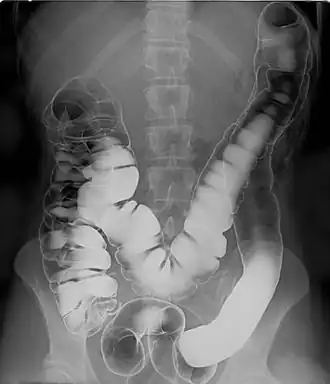

A human intestinal tract, as imaged via double-contrast barium enema, highlighting the interior of the colon

Barium sulfate is mainly used in the imaging of the digestive system. The substance exists as a water-insoluble white powder that is made into a slurry with water and administered directly into the gastrointestinal tract.

• Barium enema (large bowel investigation) and DCBE (double contrast barium enema).